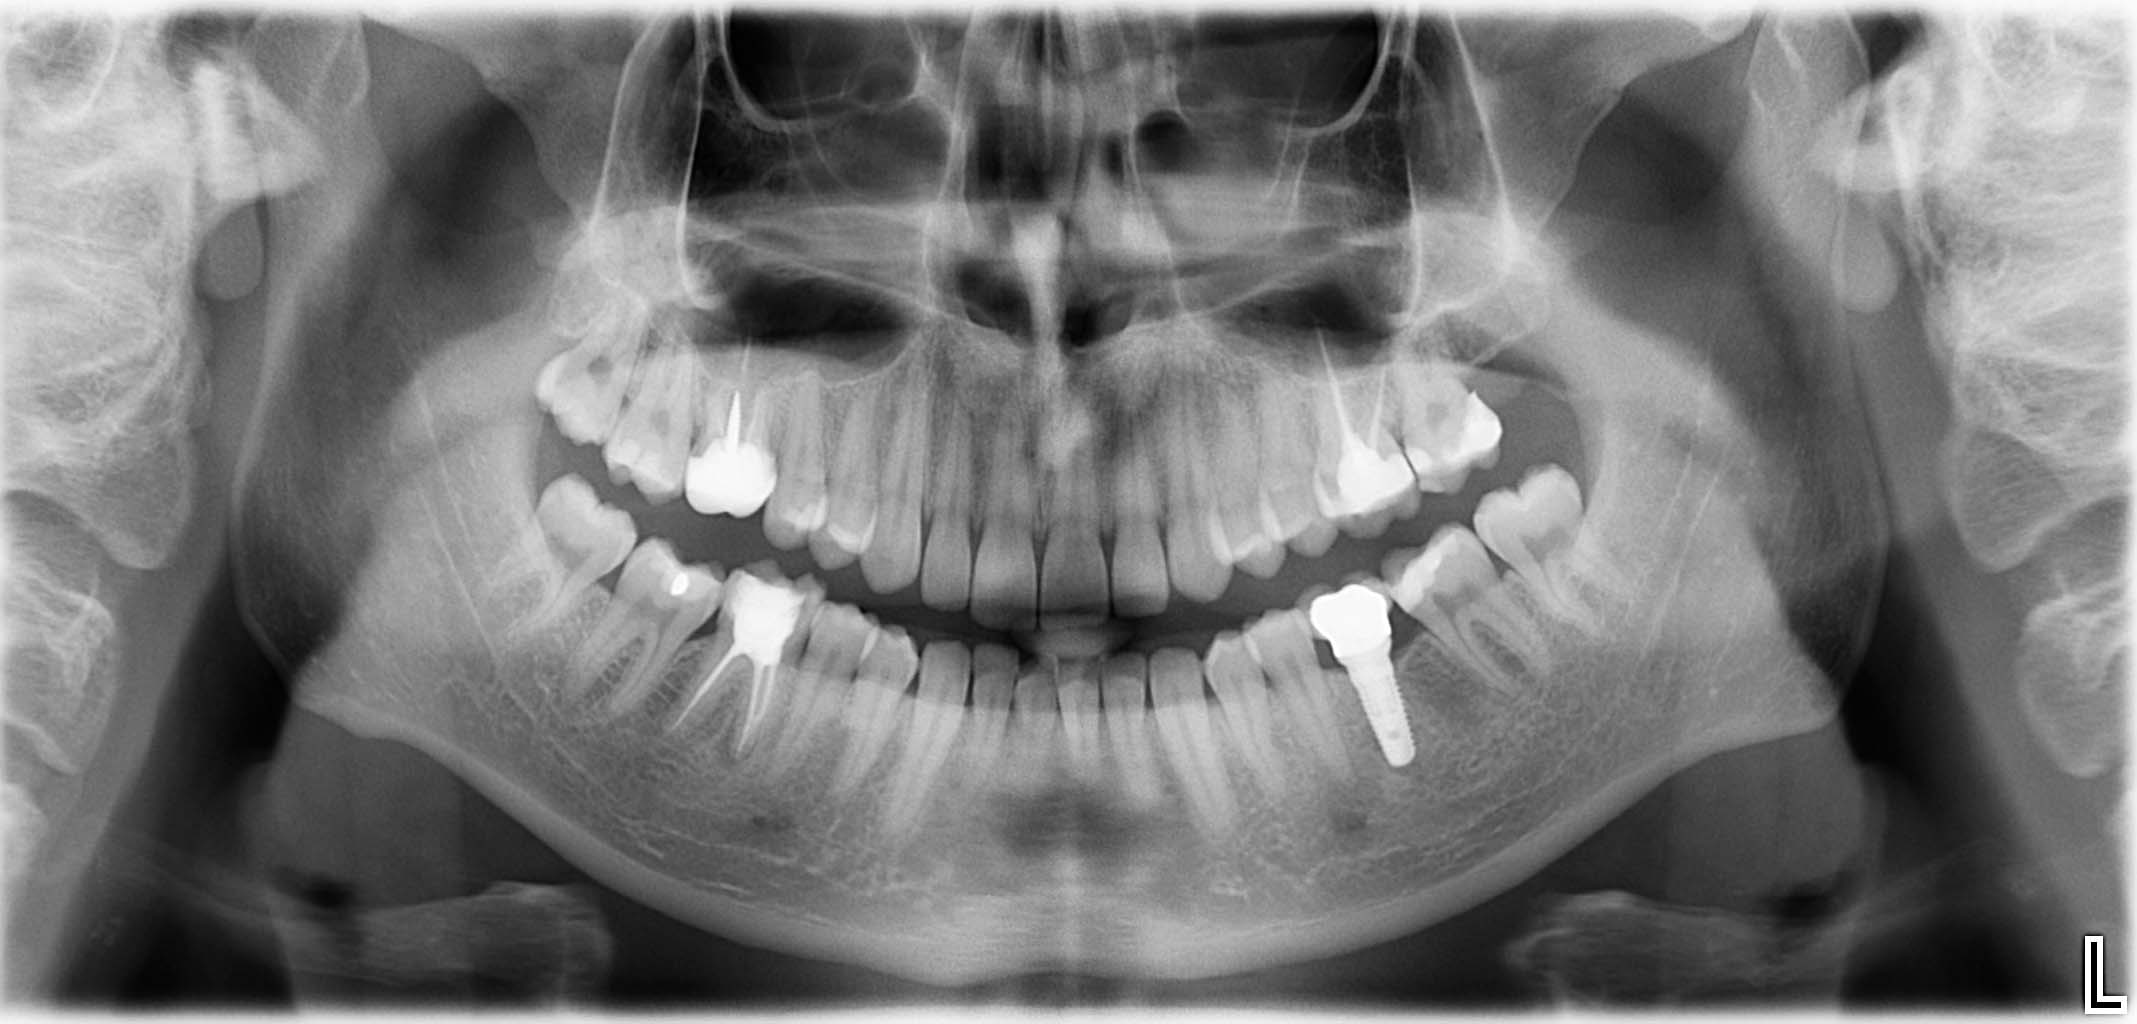

Erfolgreich implantierte Patientenfälle (klinische Fotos)